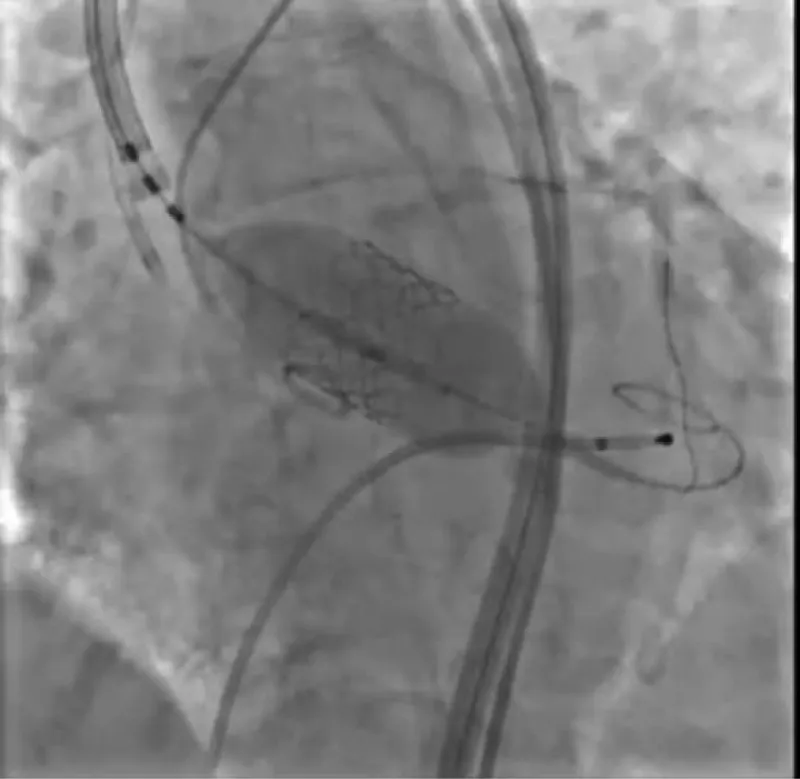

With the support of deep sedation, an angio-guided right femoral access was obtained, and a 12F introducer was advanced. We crossed the aortic valve with an Amplatzer left 1 catheter with a 0.035” wire and exchanged the wire with an extra-stiff Safari. We performed aortic Valvuloplasty with a Nucleus balloon 18 x 40 mm. (Figure 7) Then, we exchanged the wire and advanced an IMPELLA CP device, starting a protected PCI on LM. (Figure 8) An EBU 4.0 catheter was advanced, the stenosis was crossed on the Left Main (LM) and mid-Left Anterior Descending artery (LAD) using a BMW guide wire, and with the aid of a microcatheter a 0.014” Rotawire was positioned, followed by rotational atherectomy using a 1.5 mm burr on LM and mid LAD, (Figure 9) and a 2.0 mm burr on LM alone (Figure 10). This was followed by predilation with a 2.5 x 20 mm SC balloon and the implantation of a 2.5 x 32 mm Synergy drug-eluting stent (Figure 11). Then, the Left Main was predilated with a 3.5 x 12 mm NC balloon, and a 4.0 x 15 mm Xience Sierra drug-eluting stent was implanted and post-dilated with a 4.5 x 8 mm SC balloon (Figure 12). Immediate angiographic control confirmed a successful result. Then we removed the IMPELLA CP device and advanced a 14F e-sheath Edwards on the right femoral artery, crossed the aortic valve with a Safari extra-stiff wire, and performed a Sapien 3 23 mm valve implantation with a good angiographic result (Figure 13). Post-procedural echocardiographic and angiographic assessment confirmed the valve was correctly positioned, with no significant gradient and a minimal residual leak. The procedure was uneventful, and the patient was discharged on the fourth day with triple therapy: Aspirin 100 mg once daily, Clopidogrel 75 mg once daily, and Apixaban 2.5 mg twice daily. At the quarterly follow-up, the patient reported hospitalization for anemia, requiring a transfusion of 3 units of packed red blood cells. Endoscopic exams were negative, and hypochromic, normocytic anemia persisted. Given the patient’s CHA2D2-VASc score of 5, HAS-BLED score of 4, and recent dual Drug-Eluting Stent (DES) implantation, she was admitted for left atrial appendage percutaneous closure. Before this procedure, a repeat coronary angiography showed good results in the previously implanted stents (Figure 14). Subsequently, through a right femoral percutaneous approach using a 12F introducer, a 22 mm Amulet device was positioned for left atrial appendage closure (Figure 15). The procedure was completed without complications. At the 4-year follow-up, the patient presented in good hemodynamic status, with an echocardiographic ejection fraction of 55%. She continued on clopidogrel 75 mg once daily therapy.

Figure 11: PTCA on LAD.

Figure 12: PTCA on LM.